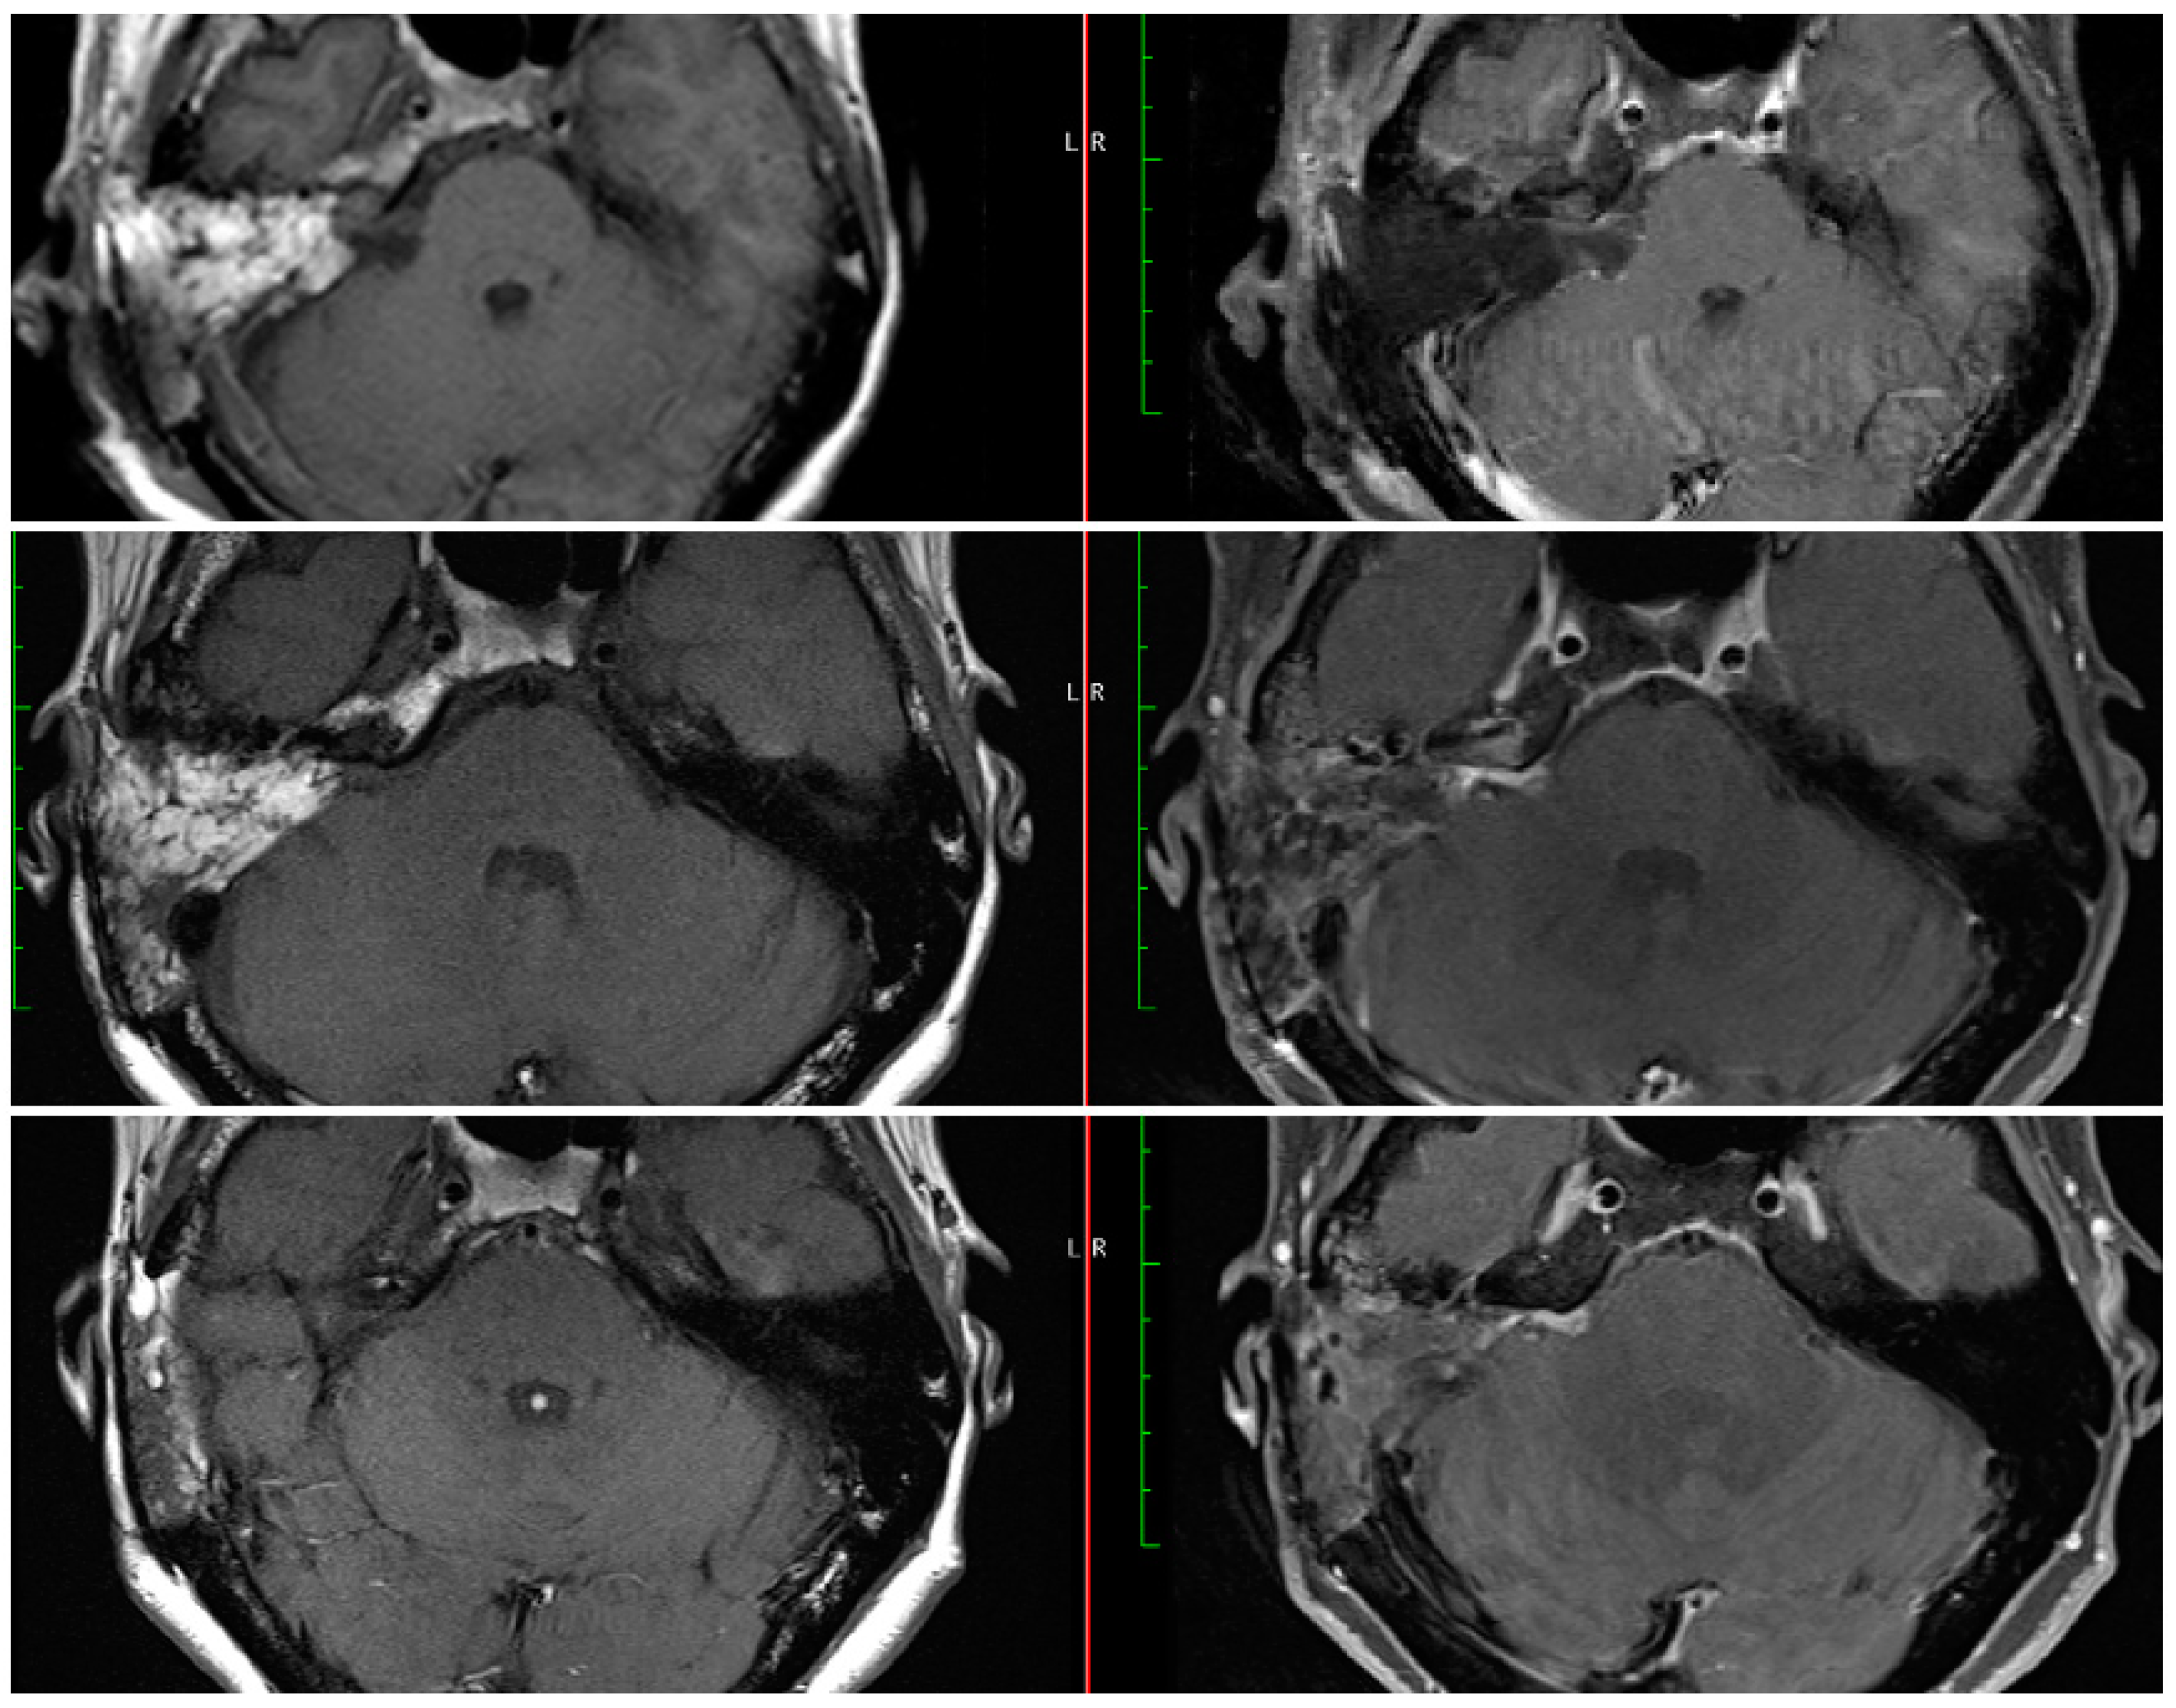

3.1.3. Follow-Up MRI Evaluation of EOR

While the timing and interval of the first post-operative MRI varies between surgeons and institutions, an early MRI during the post-operative inpatient stay could provide additional information to the surgeon. This immediate MRI is obtained on day one after the surgery at our institution. On the MRIs obtained months after the surgery, it may be difficult to differentiate scar tissue from a growing residual tumor [11,14]. An MRI obtained on post-operative day one does not include these nonspecific enhancements. The patient in Figure 2 (#6 in Table 2) had an extremely small residual about 1 mm and the immediate MRI confirmed the lack of a large residual tumor. While the later MRIs showed a larger area of enhancement than anticipated, comparison with the immediate post-operative MRI resulted in more confidence in the degree of resection and differentiation from later non-specific enhancements due to dural inflammation and/or connective tissue formation. As seen in Figure 2, the noted area of enhancement did not change in size from 3 to 15 months post-operatively. Although some studies have shown that these nonspecific enhancements can disappear with time, they may persist in other cases and continue to enhance after 5 years or longer [15,16]. This persistent enhancement can in turn result in a need for prolonged MRI surveillance. The recent survey of the ANS members revealed that a higher percentage of surgeons would follow linear enhancements for longer than 5 years and 14.3% would never stop ordering surveillance MRIs [13]. In this context, an early post-operative MRI could allow surgeons to evaluate the degree of resection and the presence of a residual tumor more accurately, and prior to any scar tissue formation. We believe that most of the changes between POD#1 and three months are attributable to enhancement seen with scarring. Hence, we anticipate that the three-month MRI may actually overestimate the extent of the residual tumor. In addition, the thickness of the obtained images can potentially result in missing small or thin residuals and a radiographic GTR should not obviate the need for continued surveillance in cases with a known residual. Furthermore, the current study was limited by its sample size and future studies will need to follow a larger cohort and compare the long-term appearances of residual tumors to those in the immediate post-operative MRIs.

Figure 2. Post-operative MRIs at day 1 (top), 3 months (middle), and 15 months (bottom) after NTR of a right sided vestibular schwannoma. The intra-operative residual estimate was 1 mm. The immediate MRI was a radiographic GTR, but the delayed MRIs were radiographic NTR with stable appearance of the area of enhancement.